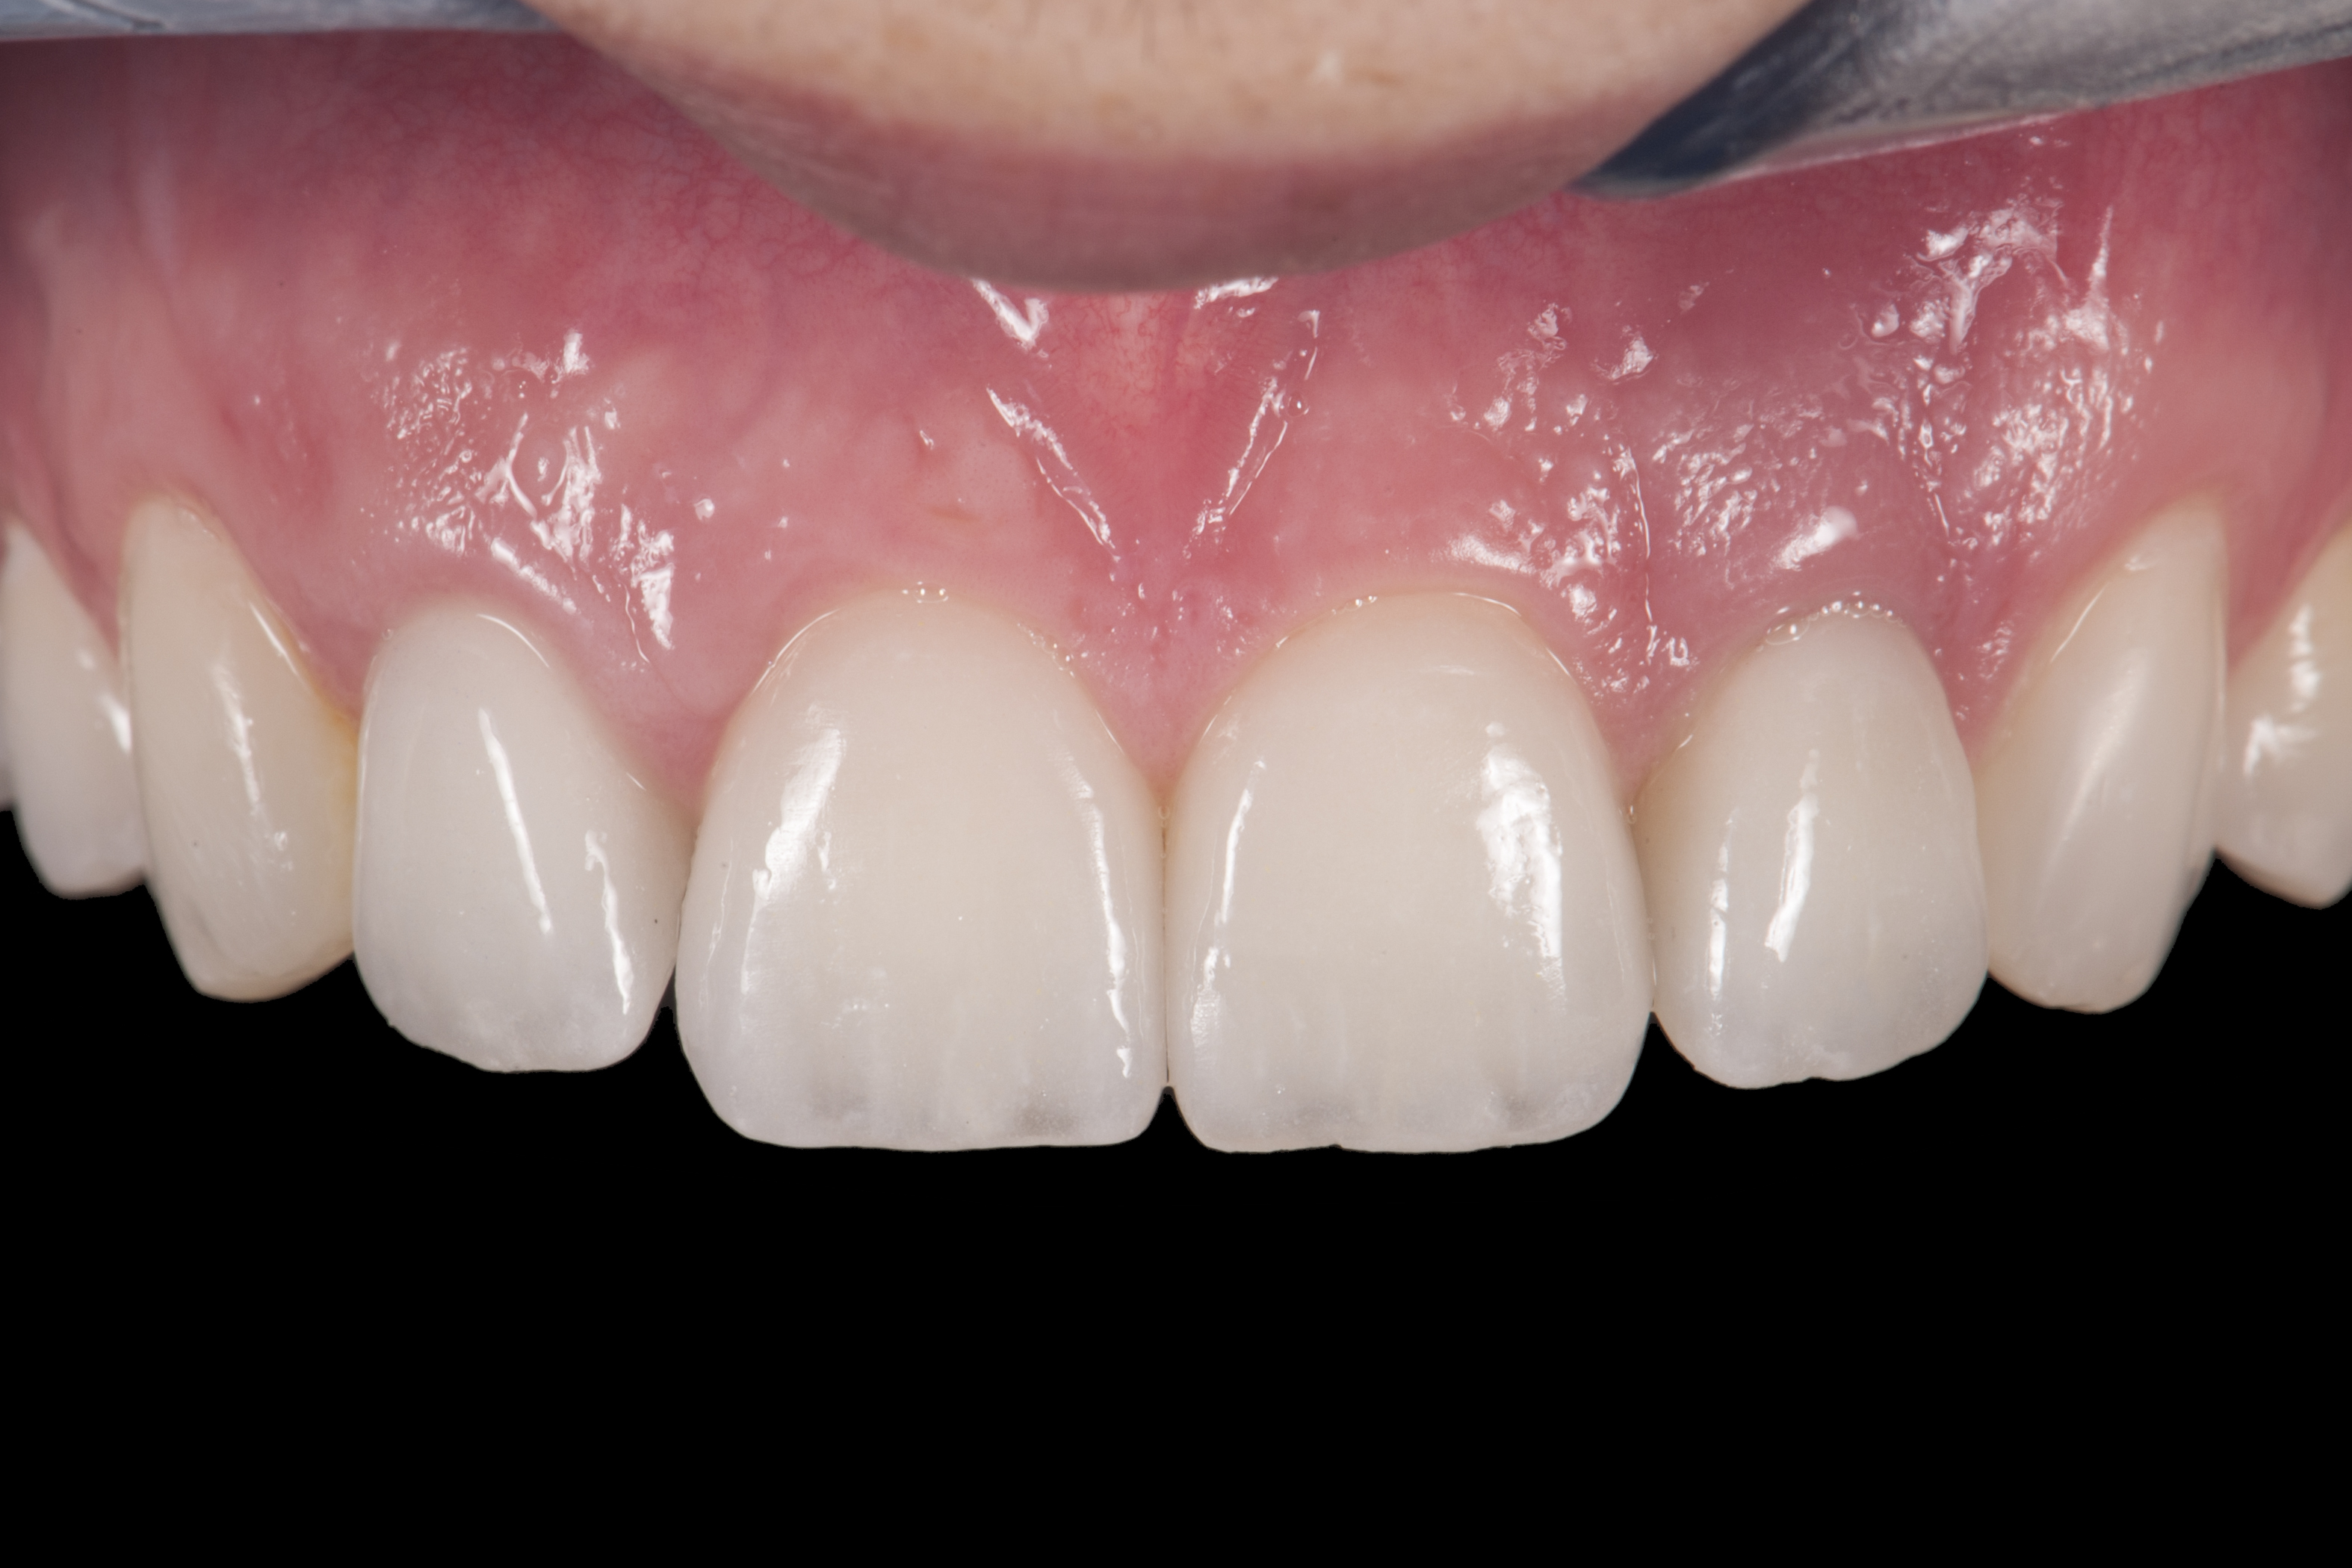

(10.) Implant crown and incisor veneers 14 days after exposure of implant.

Figure 10

(11.) Smile view, 14 days after exposure of implant.

Figure 11